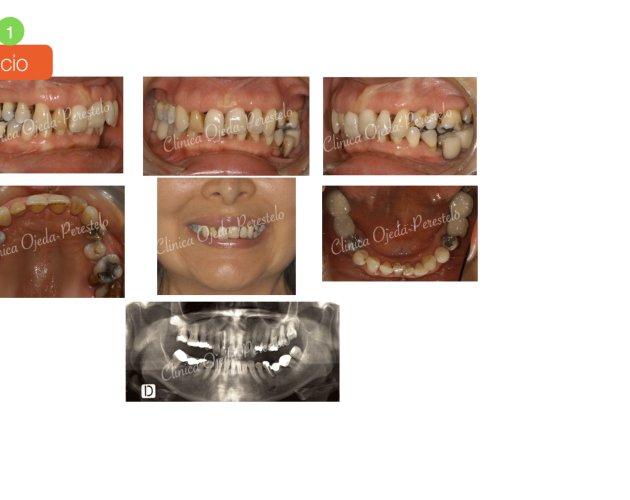

Casos de Éxito